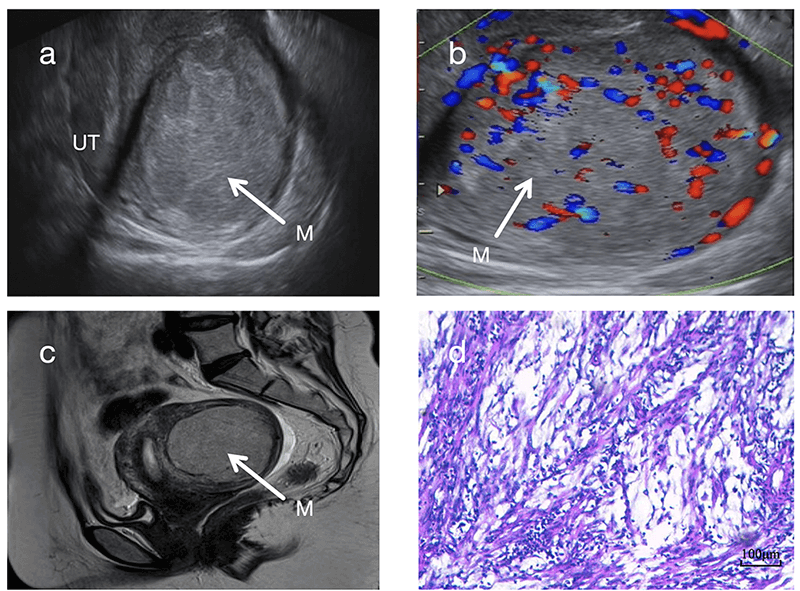

In terms of internal echogenicity, UIMT typically presents as hypoechoic, although hyperechoic appearances can also occur. The latter may be associated with increased tumor cell cellularity and pronounced inflammatory cell infiltration (Fig. 1a). Moreover, most UIMT lesions exhibit heterogeneous internal echoes, likely resulting from the irregular interlacing of collagen fibers within the tumor stroma [9].

Fig. 1.

Ultrasonographic and Pathological Images of Case 2. (a)

Sagittal 2D ultrasound image showing a hyperechoic mass in the posterior uterine

wall with a “blurred halo sign”. (b) Color Doppler ultrasound demonstrating

abundant intralesional blood flow signals (Adler grade 3) with a “colorful

mosaic sign”. (c) T2-weighted MRI revealing a slightly hyperintense mass. (a,b,c)

White arrows indicate the tumor masses. (d) HE staining (100

In this study, all 6 cases of UIMT presented as solid masses, in agreement with the findings of Bai et al. (2024) [6]. Therefore, the presence of solid components may be considered a characteristic sonographic feature of UIMT. Zhao et al. (2022) [10] described a case of UIMT containing cystic components, possibly arising from inflammatory infiltration, intratumoral hemorrhage, or cystic necrosis.

A key observation in this study was the “blurred halo sign”, identified as a typical ultrasonographic feature of UIMT. This sign is characterized by scattered strip-like or patchy hyperechoic areas within a hypoechoic background (Fig. 1a, Fig. 2a). It is clearly distinguishable from the “whorled pattern” typically observed in conventional leiomyomas (Fig. 2c). In leiomyomas, heterogeneous hypoechoic or isoechoic areas create whorled textures due to interwoven smooth muscle cells and connective tissue fibers. In contrast, UIMT lesions display more homogeneous, dense internal echoes. Its signal on magnetic resonance imaging (MRI) also appears relatively homogeneous (Fig. 1c), whereas leiomyomas generally show lower and more disorganized echogenicity (Fig. 2a,c). However, overlap in imaging features may occur when leiomyomas undergo degenerative changes, such as mixed echogenicity or cystic transformation [11]. In such instances, the diagnostic utility of the “blurred halo sign” when combined with abundant blood flow signals becomes even more prominent.

According to the latest WHO classification, UIMT includes three histological subtypes: (1) Loosely arranged myofibroblasts with mucus, rich vessels, and inflammatory infiltration; (2) Densely packed spindle cells with mucus or collagen regions; and (3) Scar-like hyperplasia with scattered inflammatory cells. All 6 cases in this study presented features of the myxoid and dense spindle-cell types (Fig. 1d), with mild cellular atypia and abundant cytoplasm—features that can lead to misdiagnosis as uterine leiomyoma or spindle cell sarcoma [25, 26]. Thus, accurate diagnosis requires an integrated assessment combining histopathology and immunohistochemistry, with ALK expression and rearrangement serving as key criteria.